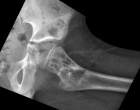

S.P. - 12 year old male with left hip pain after a minor fall

Zoom image: Radiological image Radiological image.